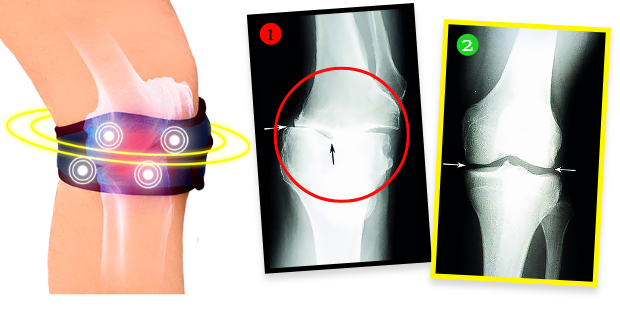

Paní Helena si po kúře nechala udělat rentgen, ukázalo se, že degenerativní změny v koleni zcela zmizeli! Lékař byl ohromen – nevěděl, co říct. Faktem je, že díky biomagnetickému pásku se stav kolena paní Heleny nejen přestal zhoršovat, ale chrupavka a jemné struktury v oblasti kloubu se zregenerovaly a koleno je opět plně funkční, stejně jako před lety. Pásek totiž vyzařuje přírodní a bezpečné biomagnetické pole, které proniká do nejhlubších tkání kloubu, vyživuje a regeneruje chrupavku, vrací jí pružnost a elasticitu, zároveň stimuluje produkci kloubního mazu, který tlumí a chrání před bolestivým třením při pohybu. Jde o plně neinvazivní a bezpečnou terapii.

„Ještě před 1,5 měsícem jsem měl zničené, praskající klouby, díky tomu jsem sotva chodil. Každý větší fyzický výkon způsobil, že klouby explodovaly bolestí. Díky tomuto pásku cítím, že mé klouby fungují jako zamlada! Potvrzují to výsledky kontrolních vyšetření RTG, USG a magnetické rezonance. Když jsem je viděl, rozplakal jsem se štěstím. Kdo by neplakal? Moje kolena jsou jako nová!”